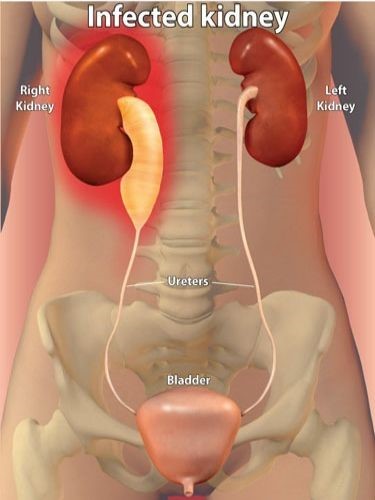

ΠΥΕΛΟΝΕΦΡΙΤΙΔΑ

Αφορά λοίμωξη των νεφρών, συμβαίνει σε άνδρες και γυναίκες με μεγαλύτερη συχνότητα στις γυναίκες λόγω της ανατομίας της ένωσης του ουρητήρα με την γυναικεία ουροδόχο κύστη. Παρουσιάζεται όταν ούρα τα οποία εμπεριέχουν μιικρόβια παλινδρομούν (ανεβαίνουν) από την ουροδόχο κύστη στα νεφρά όπου και εγκαθίστανται δημιουργώντας μια πολύ σοβαρή λοίμωξη.

Η διάγνωση γίνεται με εργαστηριακό έλεγχο με χρήση γενικής ούρων, καλλιέργειας ούρων και αντιβιογράμματος για την πιθανή ανάδειξη μικροβίων στα ούρα καθώς και τη μέτρηση των δεικτών φλεγμονής για τον υπολογισμό της βαρύτητας της λοίμωξης. Η διάγνωση γίνεται και με απεικονιστικό έλεγχο για την πιθανή ανάδειξη οιδήματος, υδρονέφρωσης καθώς και πιθανή ανάδειξη λίθου.